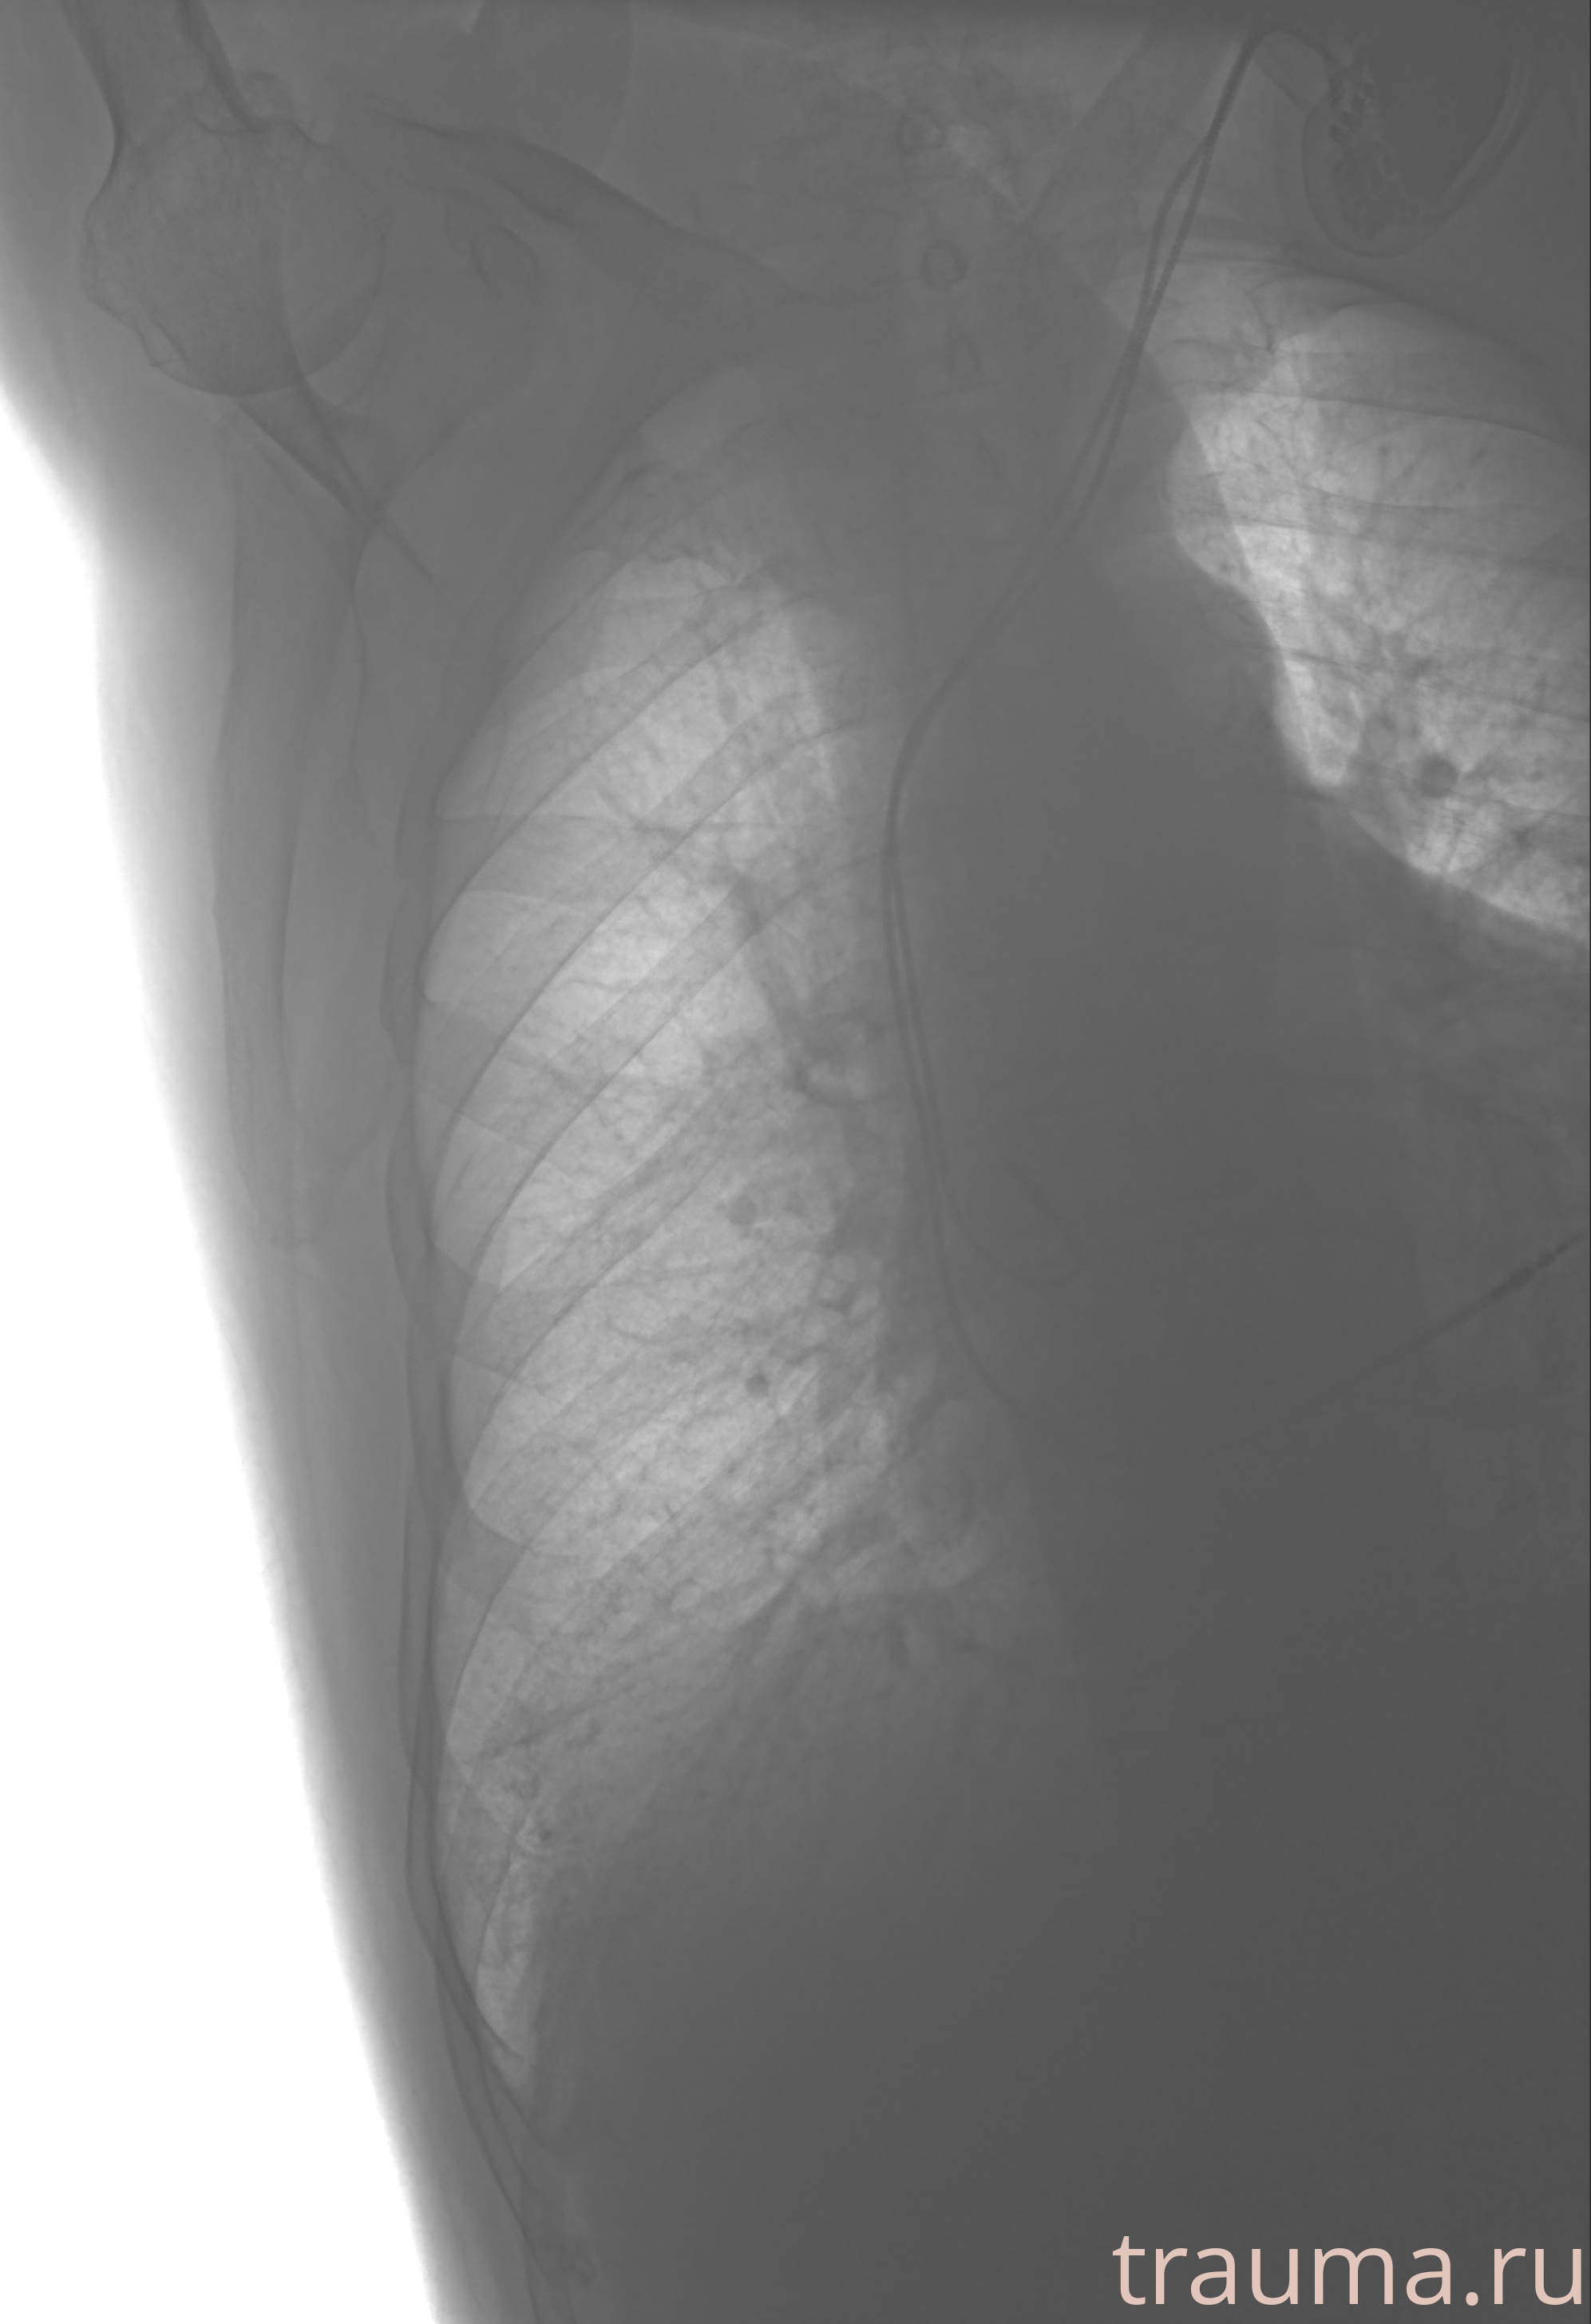

Рентген на дому: по вашему адресу приезжает врач-рентгенолог, травматолог-ортопед с мобильным рентгеновским аппаратом, проводит диагностику травмы или заболевания, делает необходимые рентгенограммы, дает рекомендации по дальнейшему лечению. Получить качественные снимки в домашних условиях возможно благодаря уникальной методике, разработанной МосРентген Центром для института  Склифосовского